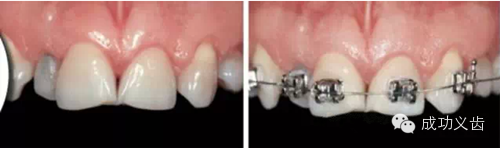

图5.Nobel Replace种植前。联合正畸治疗,以常用的Nobel Replace系统,来修复这个病例。

图6.Nobel Replace种植后。可见缺失的双侧切牙好像从牙龈里生长出来的一样。漂亮的外科、精心的软组织维护、极致的修复、和完善的口内摄影,成就了这个完美的病例。